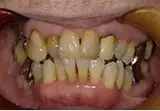

| 年齢/性別 | 70代女性 |

| 主訴 | 左下奥歯に痛みがある、全体的に治したい |

| 治療内容 | 全体的に歯周病やむし歯、根の治療を行い、仮歯を使用して咬合治療を実施。左上、右下、左下の計3本を抜歯し、右上には2本のインプラントを埋入しました。 |

| 治療期間 | 4か月(インプラントのみ) |

| 費用 | 1,116,500円税込 |

| リスク・副作用 | 炎症反応によって術後に腫れや副鼻腔炎が生じることがあります。その程度は、手術の範囲や方法によって異なりますが、多くの場合、時間の経過とともに徐々に治まります。 |